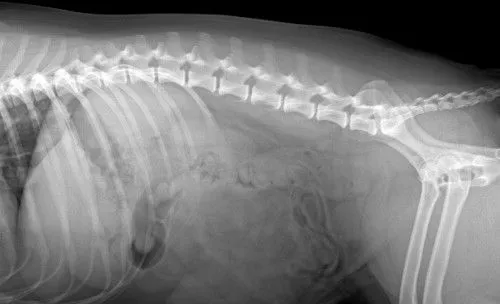

after bladder stone surgery

After Surgery